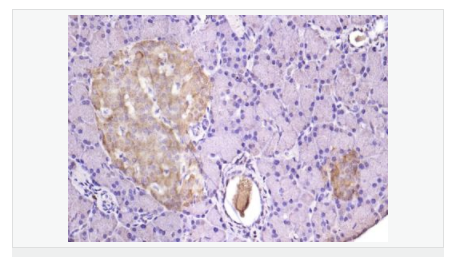

| 產品應用 | WB=1:500-2000 ELISA=1:5000-10000 IHC-P=1:100-500 IHC-F=1:100-500 IF=1:100-500 (石蠟切片需做抗原修復) not yet tested in other applications. optimal dilutions/concentrations should be determined by the end user. |

| 細胞定位 | 細胞漿 細胞膜 |